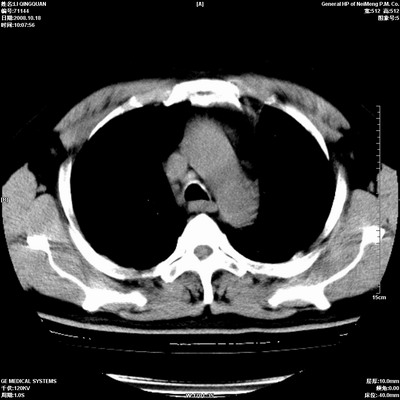

以下是引用duguo在2008-10-19 13:59:00的发言:[br]左肺上叶支气管狭窄,首先考虑中心型肺癌伴阻塞性肺炎\\肺不张.

以下是引用ybing在2008-10-19 12:58:00的发言:[br]左肺上叶阻塞性炎症-建议支气管镜进一步检查除外中央型肺癌

以下是引用随光逐影在2008-10-19 14:31:00的发言:[br]考虑左肺中央型肺癌并左肺上叶阻塞性肺炎,肺不张。